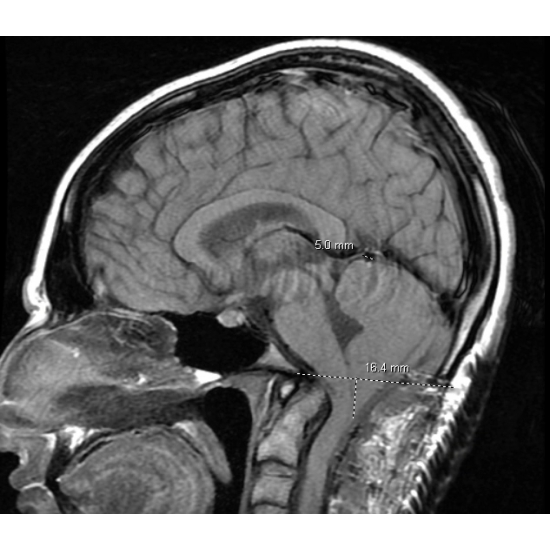

MRI cervical spine without contrast: Chiari 1.5 malformation with extensive syringomyelia of the cervical cord and partially imaged hydrocephalus of the fourth ventricle. Disc preserved in height and signal with no herniation or osteophyte complex C2-T1. Case Photo #5

MRI brain without contrast: Redemonstration of malformation with the obex 28 mm below the level of the foramen magnum. Elongation of the fourth ventricle. Case Photo #6